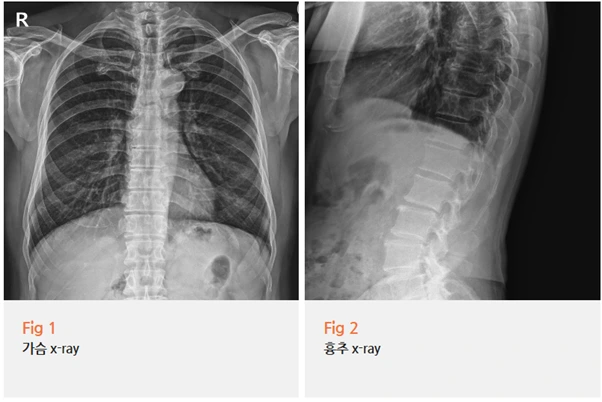

콕통증의학과에서는 우선 당일 X-RAY 검사를 포함한 기본 검사를 꼼꼼하게 진행했어요.

검사 결과와 증상 패턴을 종합해서 살펴보니, 환자분의 통증은 늑간신경통으로 진단되었어요.

내과적 이상이 없는데 가슴 쪽에 찌르는 통증이 지속된다면, 사실 늑간신경 쪽을 꼭 한번 확인해봐야 해요.

이분이 딱 그런 케이스였어요.